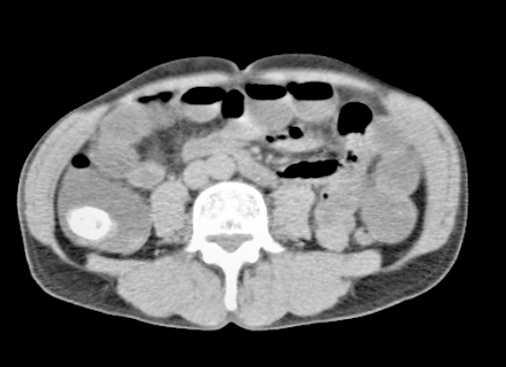

Ilustración 1 Tac con cálculo en válvula ileocecal

Fuente: Hospital de Especialidades Guayaquil “Doctor Abel Gilbert Pontón”.

Autor: Dr. Fernando Moncayo A.

Ilustración 2 Tac con cálculo en válvula ileocecal

Se presenta el caso de un paciente de sexo masculino, 68 años de edad, diabético, que debuta con dolor abdominal náuseas, vómitos, distensión abdominal intermitente con signo radiológico de obstrucción intestinal (edema interasas y signo de pilas de monedas), todos estos síntomas disminuyen luego de hidratación adecuada por lo cual se decide realizar tomografía computarizada la cual revela un cálculo de 2.5 a nivel de íleo terminal, por lo que se decide la intervención quirúrgica.